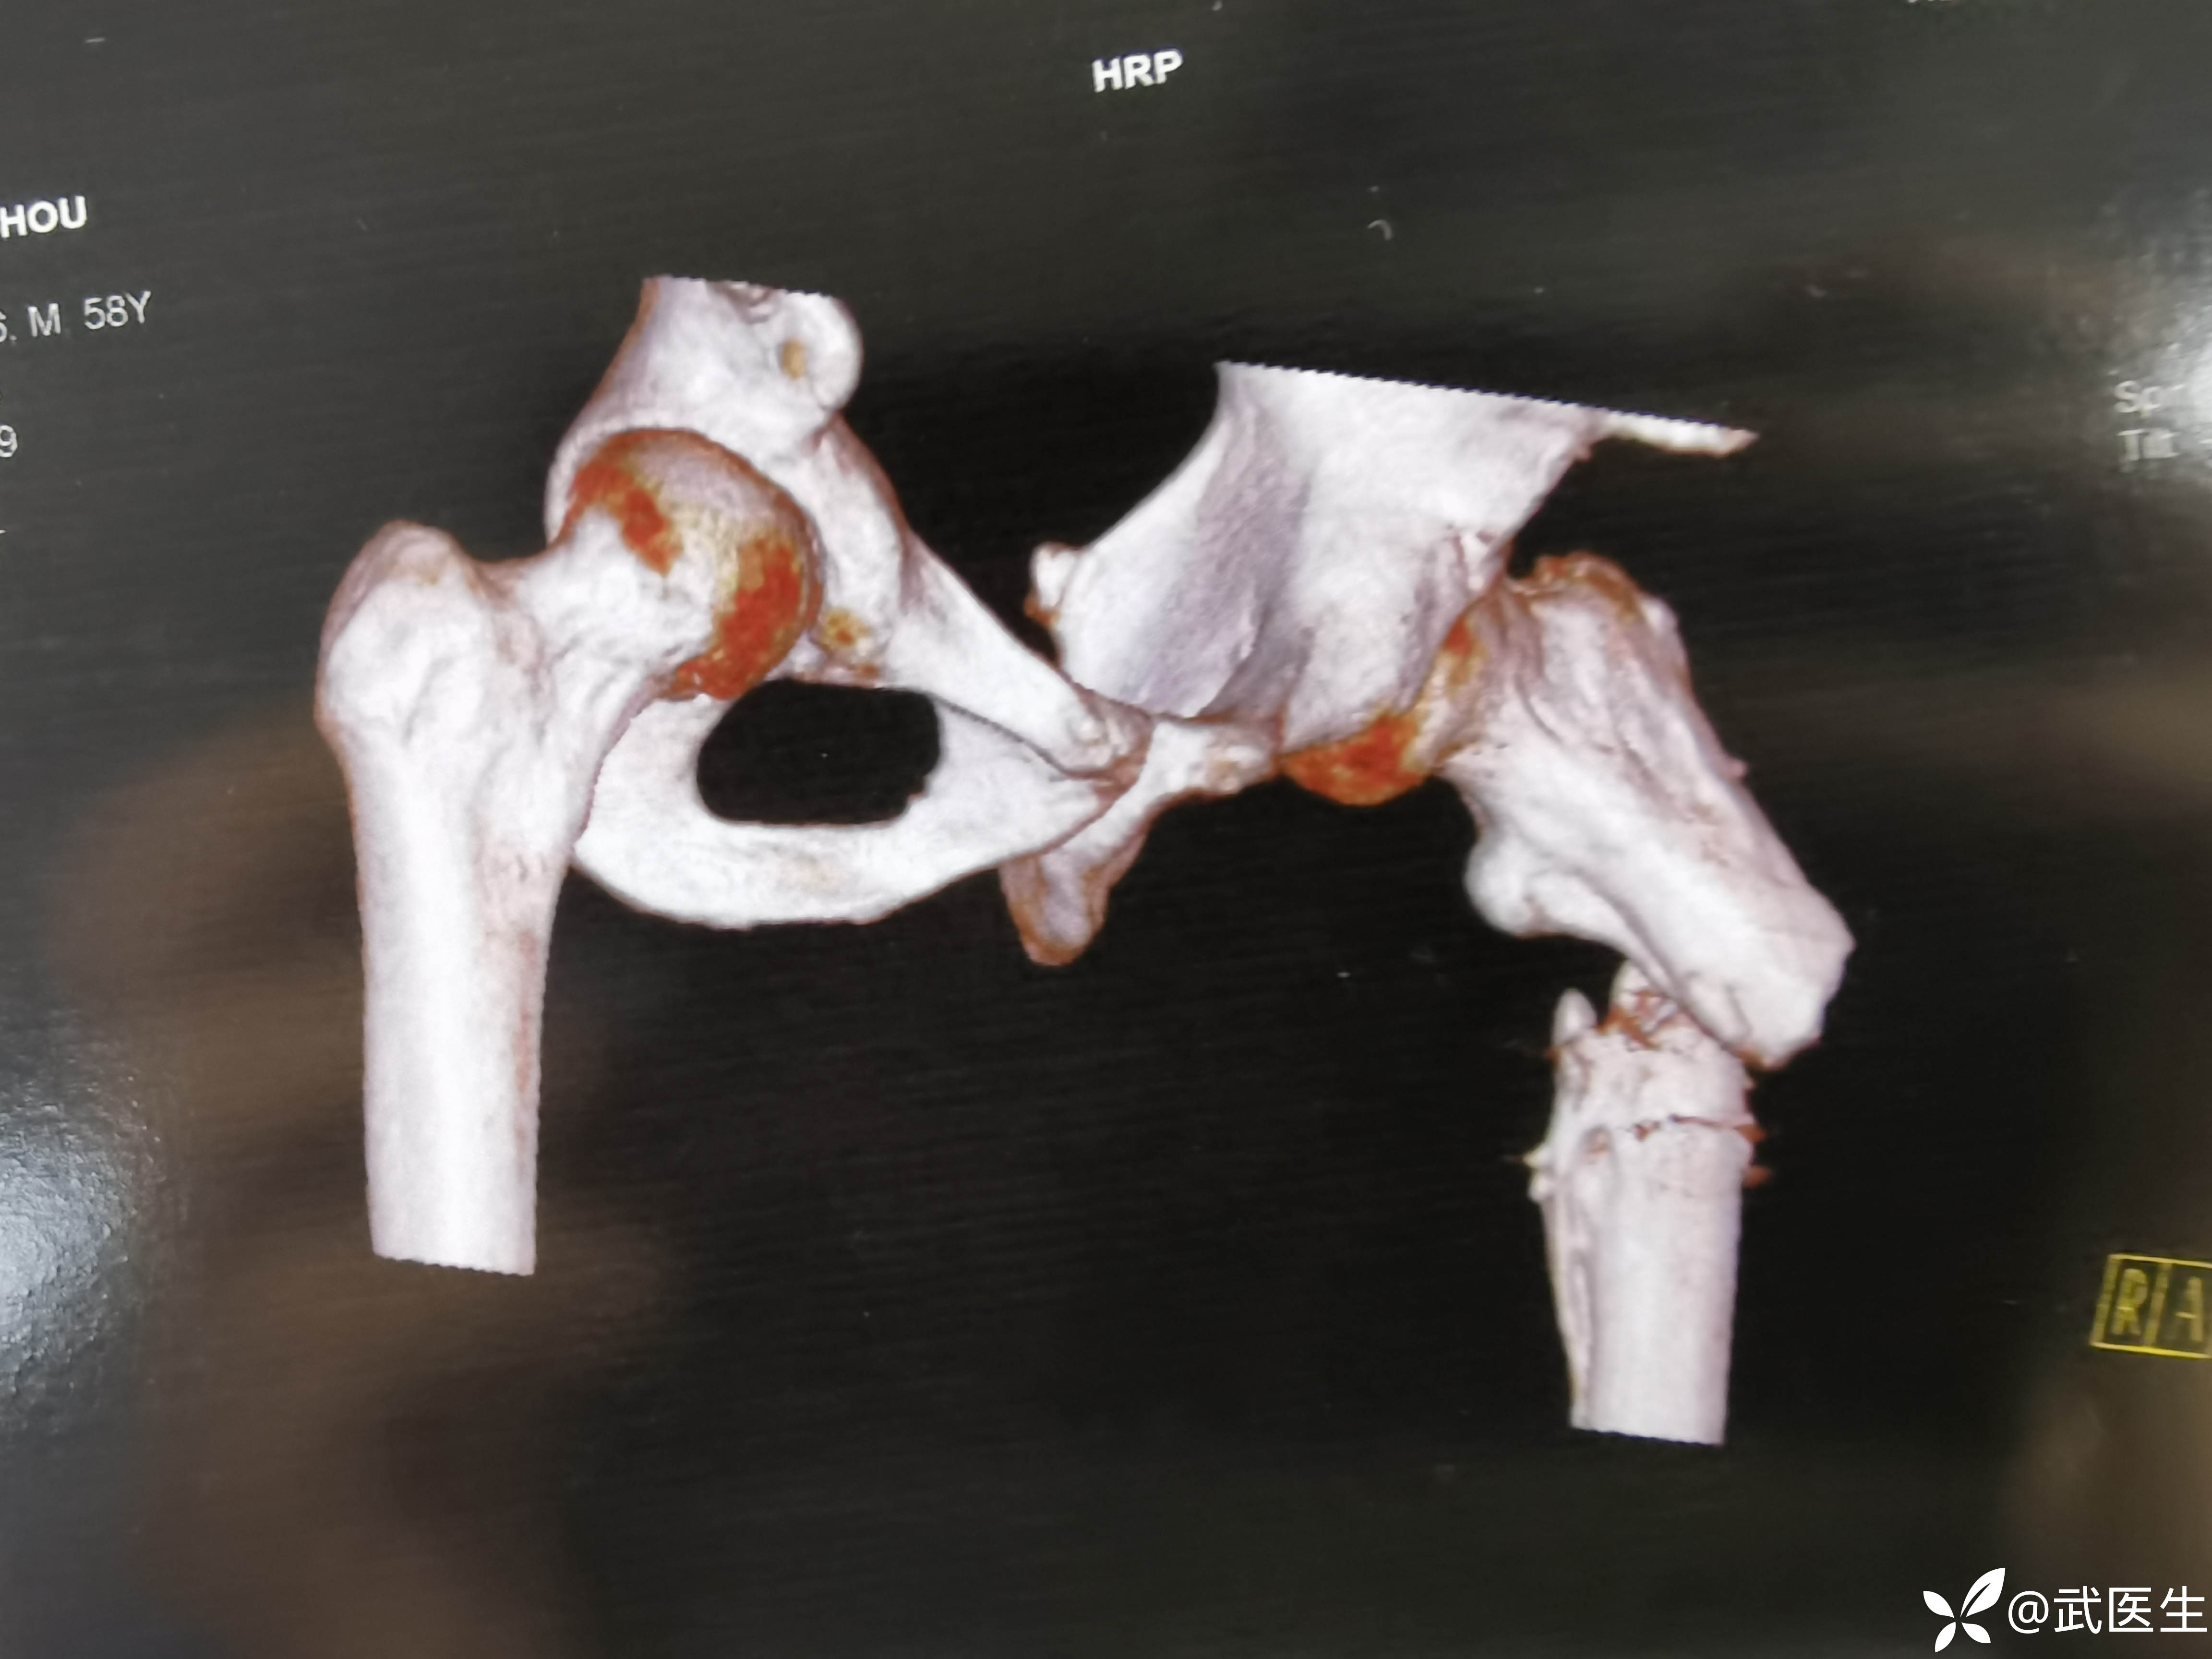

CT如下,典型股骨近端骨折移位方向